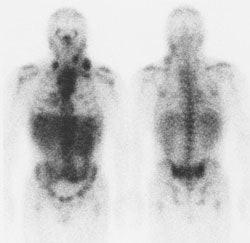

Hodgkins Lymphoma: The Ga67 scan below demonstrates nodal uptake of tracer in the neck and mediastinum in this patient with Hodgkins disease. Click image to enlarge. |